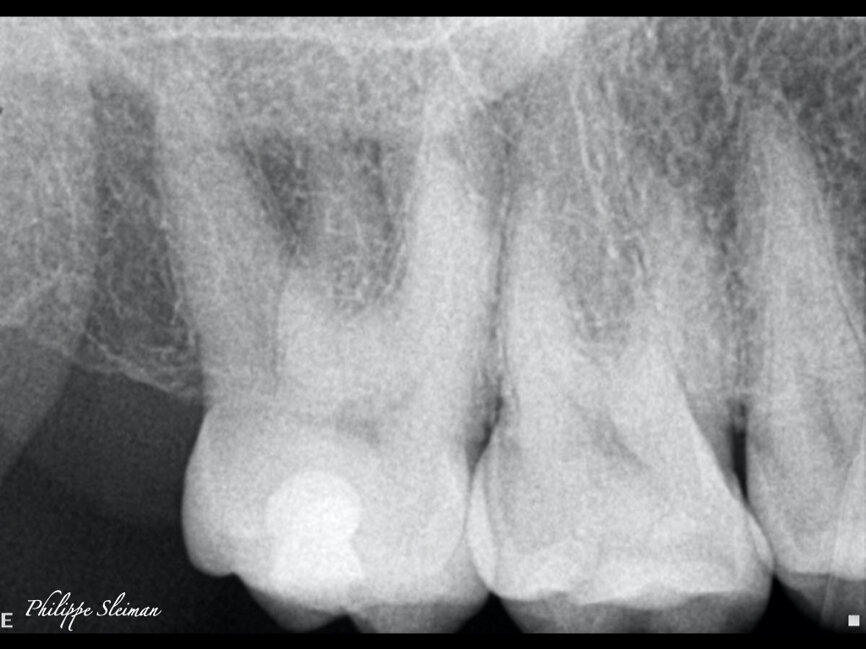

Irreversible pulpitis was causing this patient a great deal of pain. When examining the preoperative radiograph (Fig. 9), I saw doubled periodontal ligament on the mesial root, which clearly indicated a second canal in this root. The opening of the second mesiobuccal canal was very tight and very small; nevertheless, it had a separate exit.

The immediate postoperative radiograph in Figure 10 does not show it, but an image at a further 15° angle would clearly show the independent exit of the second mesiobuccal canal. A micro-CT scan of a similar anatomy—as we can never find two identical anatomies—is illustrated in Figure 11.